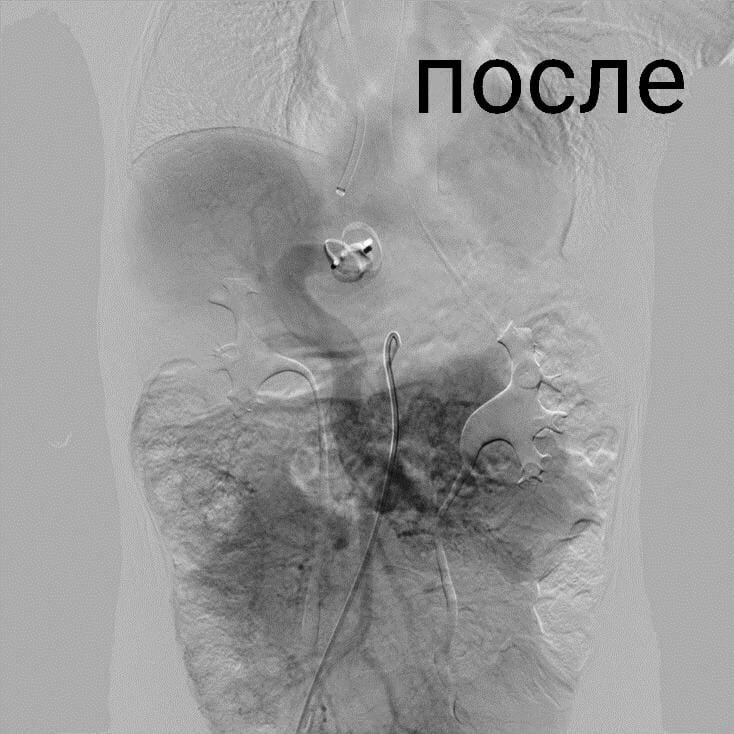

Врачи отделения рентгенохирургических методов диагностики выполнили закрытие Аранциева протока у мальчика малотравматичным эндоваскулярным методом.

«Проток закрыли с помощью специального окклюдера, - микрохирургического устройства, которое вводят по сосудам через яремную вену. Уже через неделю после операции ребенок был выписан домой. Наши врачи первыми в России начали применять эндоваскулярный метод при закрытии Аранциева протока у детей. Разработки в этом направлении шли параллельно с японскими коллегами. Первые подобные операции в двух странах были сделаны почти одновременно. В России такие уникальные методики были внедрены в практику по инициативе члена-корреспондента РАН, заведующего отделением торакальной хирургии ДГКБ им. Филатова Александра Разумовского, - рассказала детский хирург Ирина Подвойская.

С 2016 года в отделении радиохирургических методов диагностики и лечения Филатовской детской больницы (единственном в системе здравоохранения Москвы) эндоваскулярным методом прооперированы 15 детей в возрасте от одного года до 15 лет.